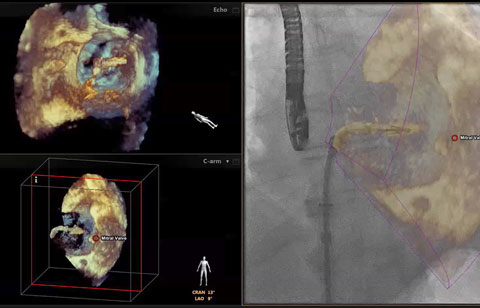

بعد تشخيص مريض بارتجاع الصمام الميترالي، ما هي خيارات العلاج المتوفرة له؟ إذا لم يكن مرشحًا للخضوع لعملية القلب المفتوح، يمكنك التفكير في معالجته عبر إصلاح الصمام الميترالي باستخدام القسطرة (TMVR). وفي يومنا الحالي، تؤمن حلول التصوير المبتكرة والأجهزة المتوفرة حديثًا خيارات جديدة لبعض المرضى.